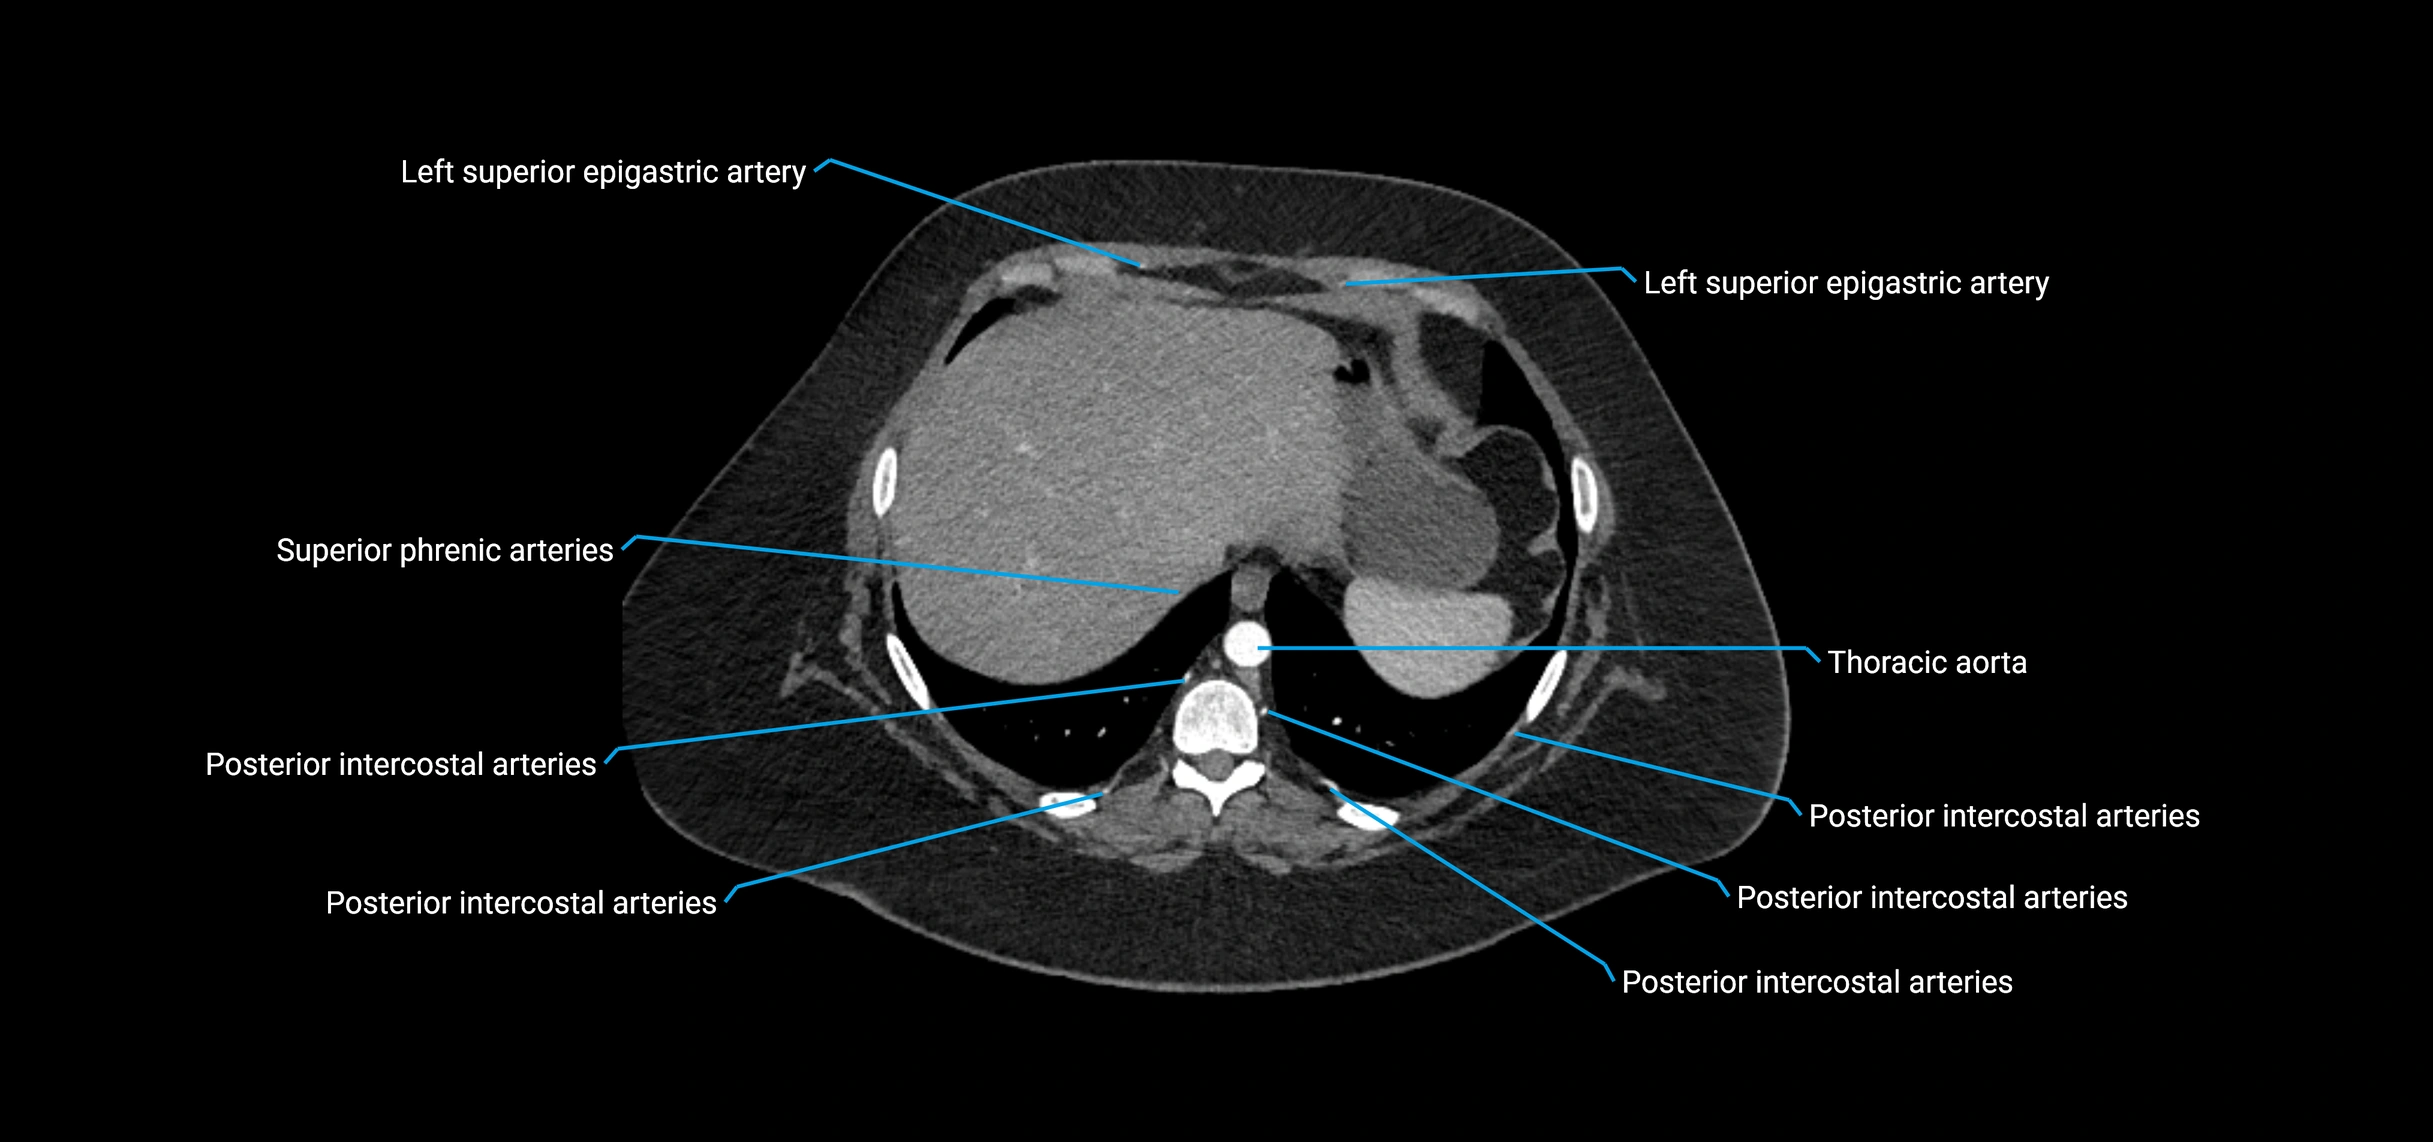

MRI Appearance

T1-weighted images:

• Flowing blood appears as a signal void (black lumen)

• Vessel wall appears as a thin hypointense rim; retroperitoneal fat enhances contrast

T2-weighted images:

• Lumen remains a signal void due to flow

• Adjacent edema, hematoma, or aneurysm wall thrombus may appear hyperintense

MRA (Magnetic Resonance Angiography):

• Contrast-enhanced MRA provides high-resolution imaging of the aorta and its branches

• Allows 3D reconstruction of visceral, parietal, and terminal branches

• Excellent for evaluating aneurysm size, dissection flap, stenosis, or preoperative planning

• Non-invasive alternative to conventional angiography